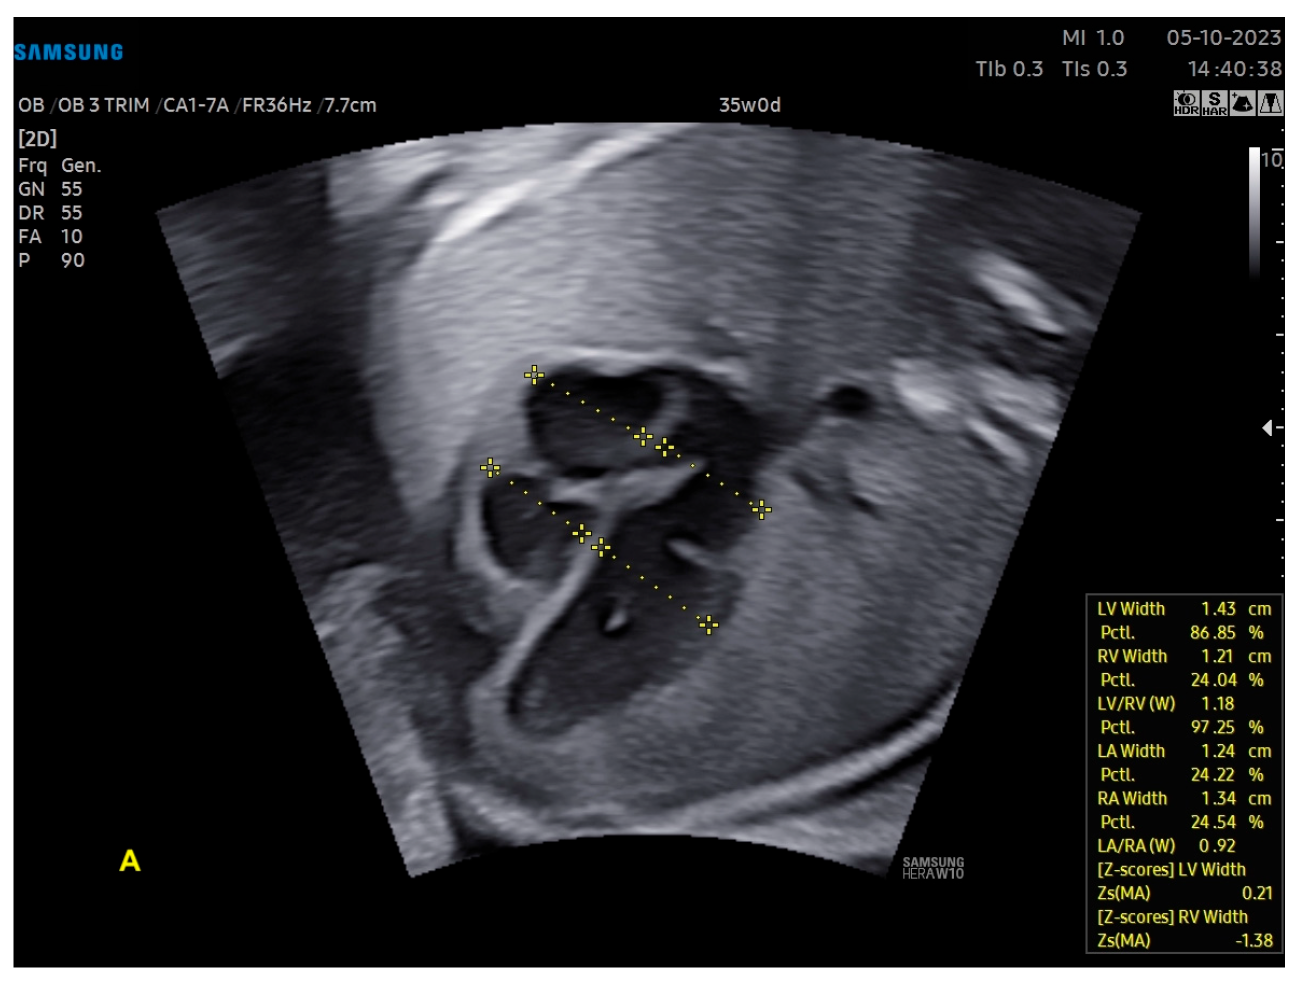

- Scharf, J.L.; Dracopoulos, C.; Gembicki, M.; Welp, A.; Weichert, J. How Automated Techniques Ease Functional Assessment of the Fetal Heart: Applicability of MPI+™ for Direct Quantification of the Modified Myocardial Performance Index. Diagnostics 2023, 13, 1705. [Google Scholar] [CrossRef] [PubMed]